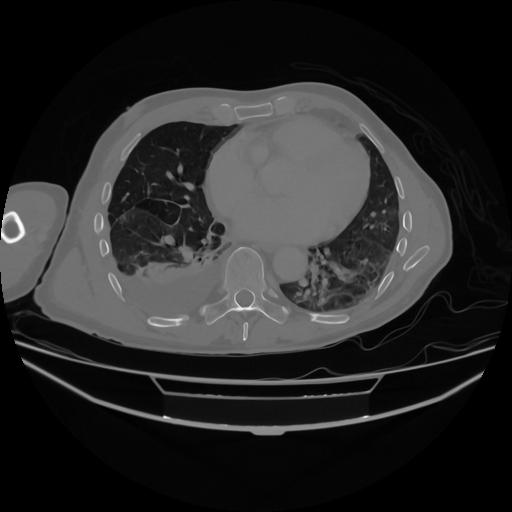

5 CUERPO,CE,Vol,1.0,CUERPO,,